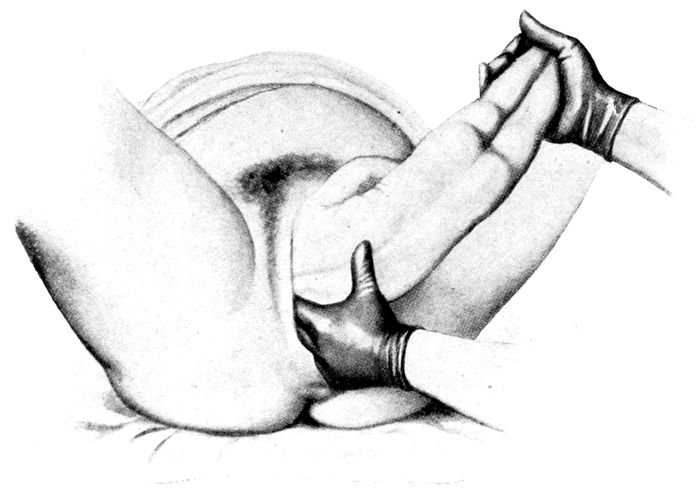

Extraction of the breech |

170 |

| |

| 64. |